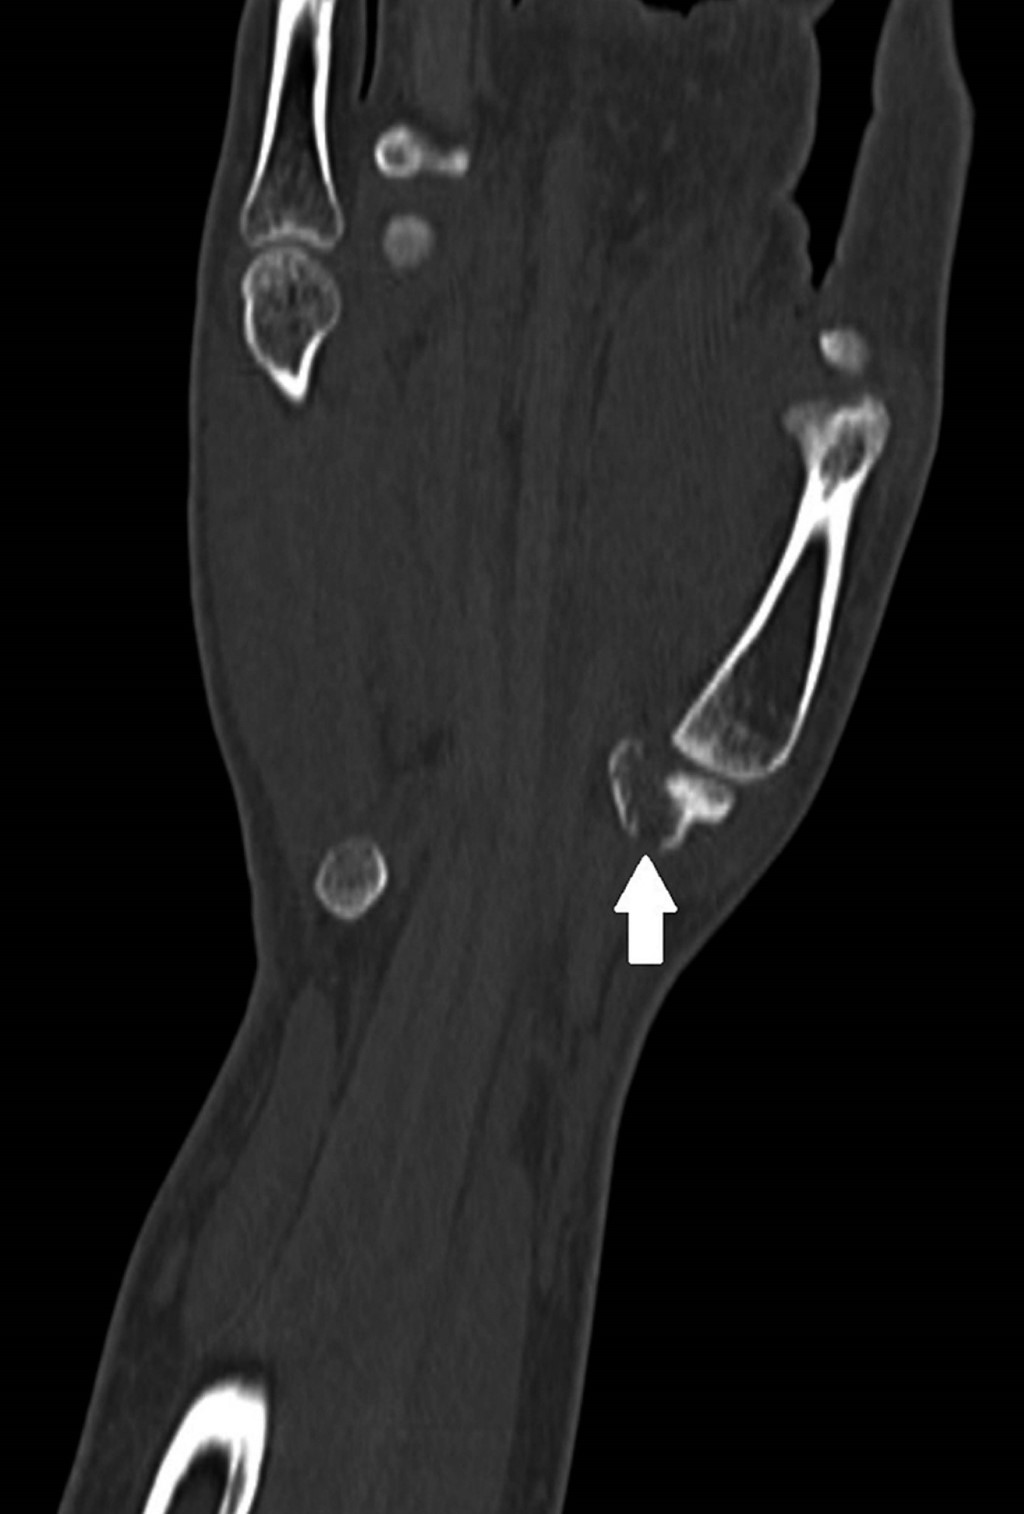

Computed tomography (CT) scan reveals a hamate bone fracture without apparent misalignment (Figure 1) and a type I trapezium tuberosity base fracture (according to Walker's classification) with a 0.2 cm fragment distance, without significant misalignment [ICD 10-S62] (Figures 2 and 3).

Figure 2